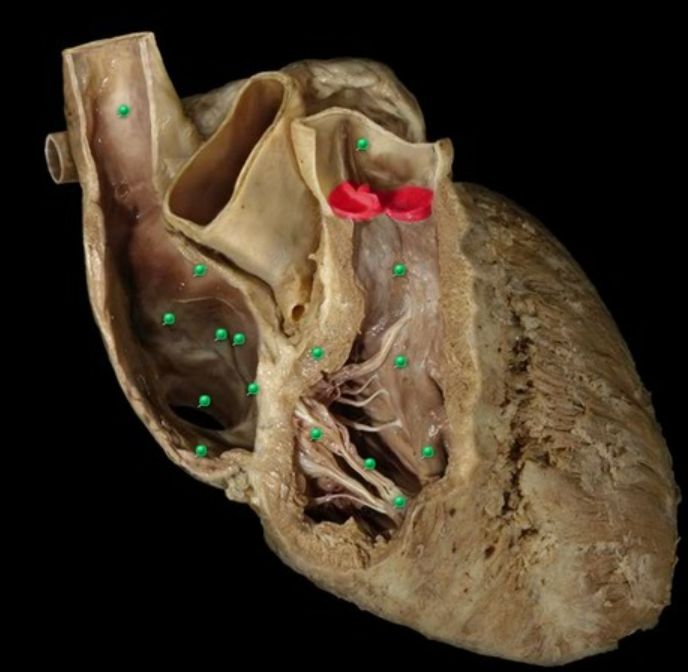

Name the valve and list the components of the valve

Aortic Semilunar Valve

nodule

lunulae

cusps